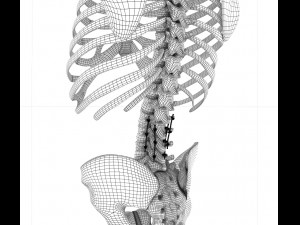

spinal fixation system - titanium bracket 3D 모델

spinal fixation system - titanium bracket. human spine, spinal cord, sacrum and fixation system medically accurate high quality 3d model.

hi-poly 3d model of human spine with internal structure.

you can control polygons by using meshsmooth function . 프린트 준비: 아니오

더 보기hi-poly 3d model of human spine with internal structure.